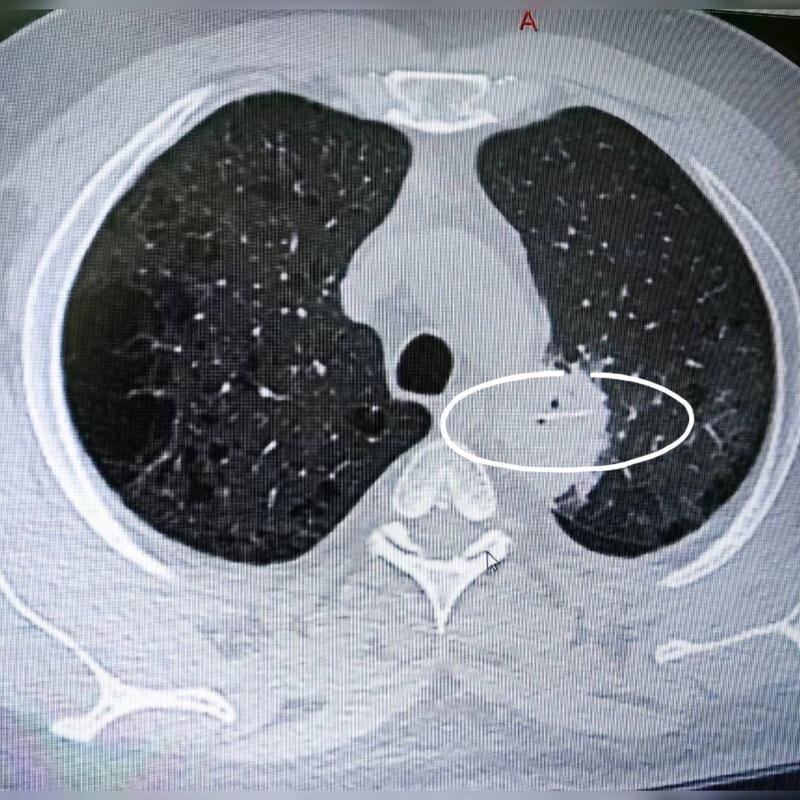

В местной поликлинике ему провели компьютерную томографию и выяснили причину телесных страданий пациента:

- После проведения КТ выяснилось, что кость пробила пищевод, мигрировала в грудную полость и вызвала гнойное воспаление в левом лёгком. Пациента экстренно направили в Сургут, где местные торакальные хирурги провели открытую операцию — торакотомию и частичную резекцию лёгкого.